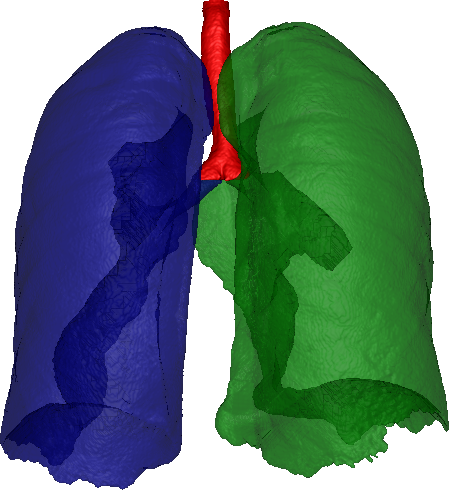

After coarse airway segmentation, we perform a left and right lung segmentation to identify a region of interest for later vessel detection. A coarse lung segmentation is obtained using Otsu’s optimal thresholding method [14]. With a connected component analysis, the lung is selected and a 3D hole filling is applied to include vascular structures. The two lungs always merge through the airways, but in some datasets the border between right and left lung is hardly visible, resulting in connected lungs. The airway segmentation is used to separate the coarse lung segmentation. Using a graph representation of the skeleton from the airway segmentation, we detect the carina (where the trachea splits into the left and right main bronchi), and assign different labels to the trachea, right and left bronchi. To label the voxels in the coarse lung segmentation, we calculate shortest paths to the labeled airway tree, thus, splitting it into left and right lung. As a cost function for the shortest path algorithm, we use the gradient magnitude of the CT image and the coarse lung segmentation without the airways, where we give a larger weight to the gradients to prevent connecting via short cuts from touching left and right lungs. We found a fraction of for the gradient weight, and a weight of for the lung segmentation without the airways to perform well in the labeling of our datasets.

As a final step, to remove holes caused by vessels and other high intensity structures inside the lung, the airways are removed from the lung segmentation, and a morphological closing operation is applied several times at each lung separately. We use a six-neighbourhood star-shaped structuring element and 10 closing operations. These parameters remain constant for all datasets. This ensures that the lung segmentations contain the whole lung. The different steps of the lung segmentation can be seen in Figure 4.

The lung segmentations from the 24 patients included all lung tissue and pulmonary vessels, which has been verified through visual inspection (Figure 5). Processing time for the lung segmentation was on average 132 seconds.